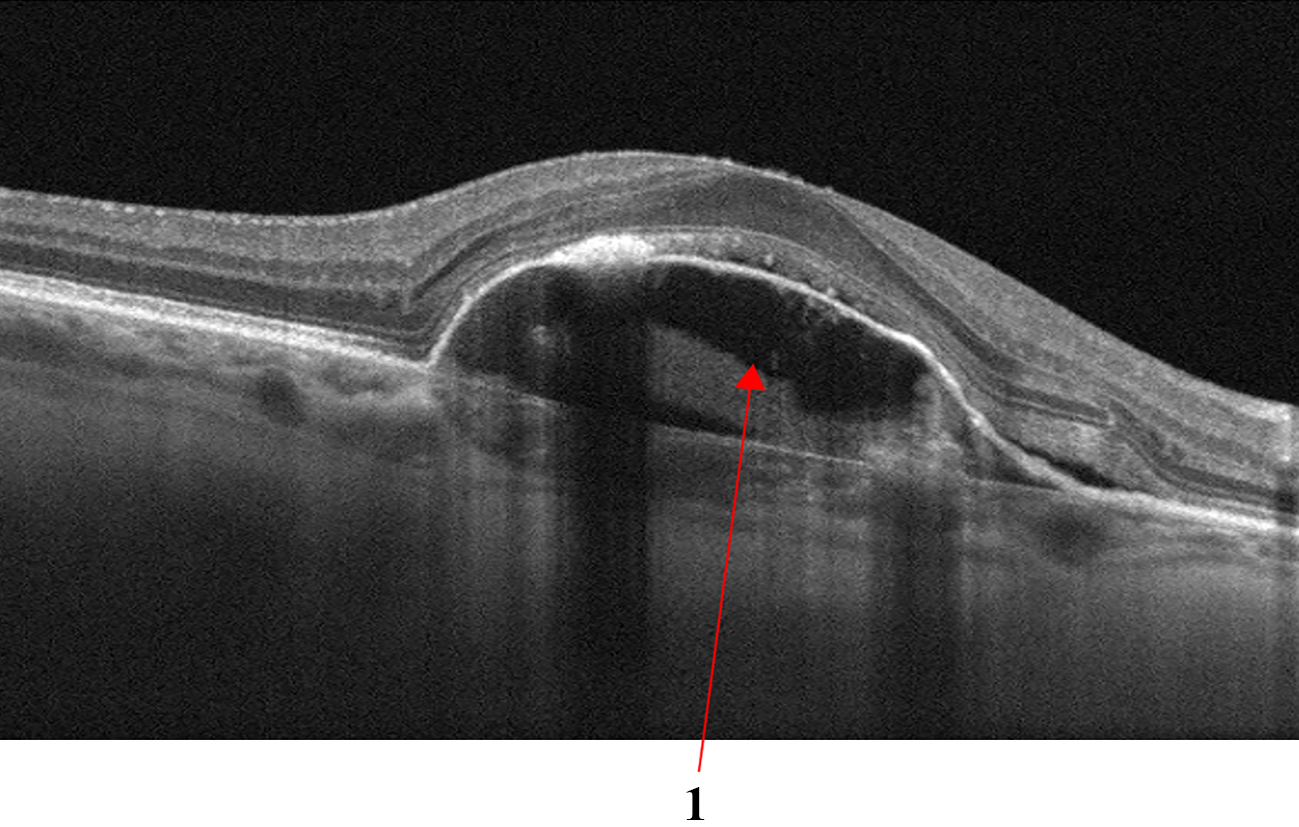

Fig.3 shows examples of AMD: the retinal profile is deformed, and the normal foveal architecture is disrupted. In Fig.3a the inner retinal layers are thinned and contain outer retinal tubulations or cystic spaces, highlighted with number 1. Subfoveolarly, a hyporeflective region is visible beneath the retinal pigment epithelium - in Fig.3a highlighted with number 2. Hyperreflective coloration of the choriocapilaris below the RPE layer atrophy is apparent. Local and diffuse decreases in the thickness of the choriocapillaris layer. Fig.3b shows different fluid-filled spaces in the macular that may accompany the clinical features of AMD:

Refer to caption

((a)) Markers

((b)) Types of fluid

Figure 3: Age-related Macular Degeneration (AMD). Markers (a): 1 - outer retinal tubulation or cystic spaces; 2 - Subretinal fibrosis causing distortion of the macular and hyporeflectivity of the underlying choroid. Types of fluid (b): 1 - subretinal fluid; 2 - intraretinal fluid; 3 - sub-retinal pigment epithelial fluid accumulation.